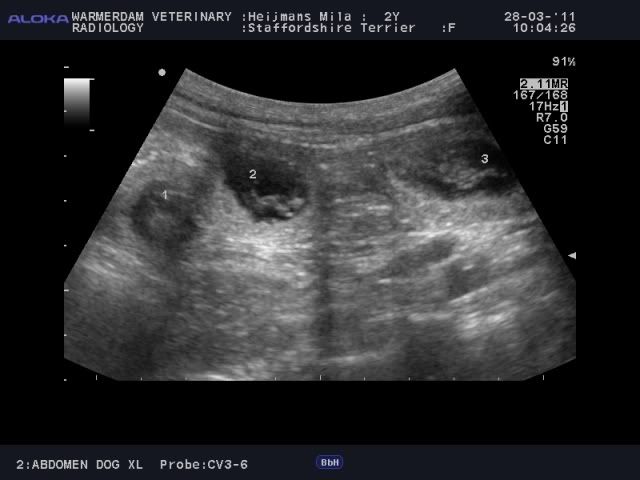

Dirk's Red Ruby (Neela)X Daydreamers Nothing Else Matters (Boedha)

Neela is 28 februari en 1 maart gedekt.

28 maart heeft ze een echo gehad en er zijn 10 a 11 pups geteld.